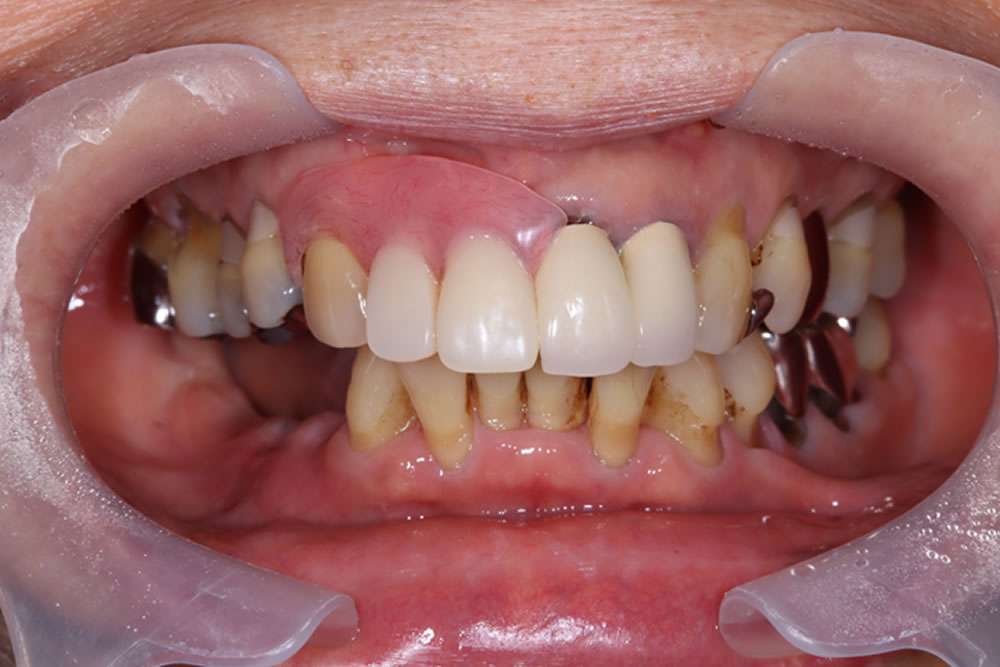

上下顎にプロビジョナル(精密仮歯)装着完了

最終的な上部構造(人工歯)を装着・治療完了

プロビジョナル(精密仮歯)での経過が問題なかったため、最終的な上部構造(人工歯)を作製・装着し、治療完了となりました。

治療前後の比較

インプラント治療により、固いものもしっかり噛めるようになったとのことでした。また、歯肉移植を併用したことで、インプラント周囲の清掃性も向上しました。